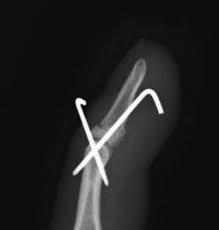

手術療法

骨の転位が強く、骨癒合乏しい場合は手術療法を選択します。

手術方法は①プレート固定、②ピンニング固定、③スクリュー固定